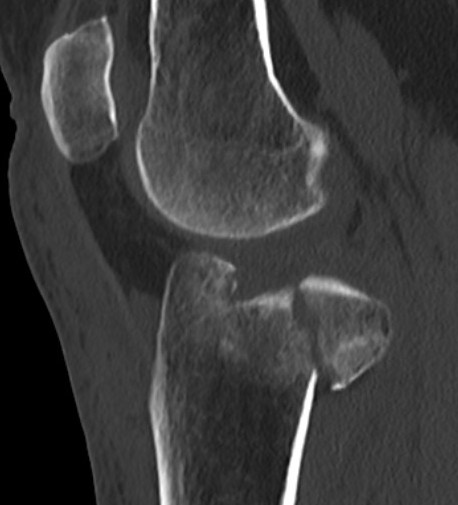

Posterolateral Tibial Plateau Fractures

Definition

- fracture in posterior half of lateral tibial plateau

- very difficult to access with standard anterolateral approach

Options

1. Trans-fibular neck osteotomy + anterolateral approach

2. Posterolateral approach + anterolateral approach